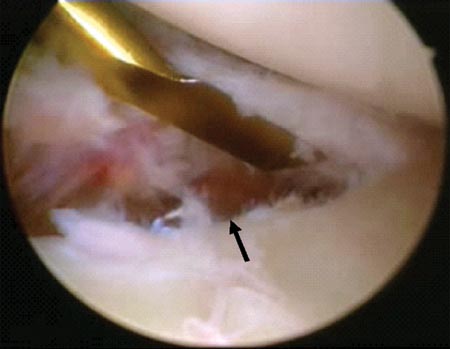

El plan preoperatorio ayuda enormemente al cirujano a la hora de realizar el posicionamiento artroscópico en la búsqueda del o los fragmentos óseos para su posterior reducción y fijación. A nuestro conocimiento es importante realizar el menor debridamiento posible de los fragmentos óseos particularmente en fracturas conminutas. Esto evita la desperiostización de los mismos y facilita su posterior reducción artroscópica. En esta serie de casos el examen articular o subacromial del lecho de la fractura no fue considerado una rutina y solo fue realizado en solo 4 casos debido a múltiples intentos fallidos en la reducción del o los fragmentos óseos por la interposición de los tejidos.

Si la reducción de los fragmentos es correcta en las imágenes por radioscopía, la fijación temporal de los fragmentos óseos con clavijas percutáneas es llevada a cabo. Posteriormente y según el tamaño de los fragmentos se utilizan tornillos canulados de 2.7 mm, 3,5 mm y/o 4.5 mm. Es importante remarcar nuevamente la no resección de los tejidos blandos (manguito rotador) de los fragmentos óseos. En 4casos de fracturas conminutas la reducción y osteosíntesis de los fragmentos fue lograda a través de los tejidos blandos y no del propio tejido óseo. Si la reducción de los fragmentos no es correcta la inspección del lecho de la fractura, primero a nivel articular y luego a nivel subacromial, es llevada a cabo con el fin de facilitar la misma mediante la remoción de tejidos interpuestos. En todos nuestros pacientes fueron colocados no menos de 3 tornillos de fijación (Fig. 1 y 2).

Figura 2A: Luxación anterior con fractura conminuta y desplazada del troquiter./ Figura 2B: Lesión articular asociada. Desprendimiento Anterior del labrum glenoideo hora 12 a 4./ Figura 2C: Espacio Subacromial: Reducción artroscópica de la fractura sin desperiostización del fragmento óseo.

Figura 2D: Flecha negra: Clavija percutanea mantiene la reducción. Flecha Amarilla: línea de fractura./ Figura 2E: Osteosíntesis con tornillo canulado de 3.5 mm./ Figura 2F: Resultado. Escalón superior de 2 mm. Reparación de Bankart y SLAP.